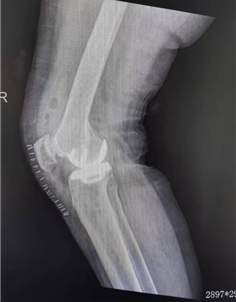

田女士今年59岁,近8年来一直饱受膝关节疼痛困扰,到多家医院就诊均被诊断为膝关节骨性关节炎(OA),建议行全膝关节置换手术(TKA),长期口服止痛药物,经济负担不小不说,镇痛药对肝肾功能以及胃肠道的健康也产生了不小的影响,后至我院关节外科就诊,经过详细的查体和影像学评估(正侧位片,内外翻应力位片和Rosenberg位片),我们发现田女士膝关节内侧间室存在骨对骨(BOB)情况,确实患有膝关节骨性关节炎,但是我们需要在前面增加一个前缀:膝关节前内侧骨性关节炎(AMOA),入院后田女士接受了一台保膝手术——单髁置换(UKA),结合我院开展多年的关节外科ERAS理念,田女士术后当日即下床活动自行如厕,第二日步行到放射科复查术后X线后返回,围手术期全程无痛体验。

田女士手术前的膝关节X线片,正位可见内侧间室骨对骨(左,红色实线),侧位可见平台前内侧骨磨损(右,红色虚线)

田女士接受UKA手术后的X线片,磨损的内侧间室已经完全被修补替代。